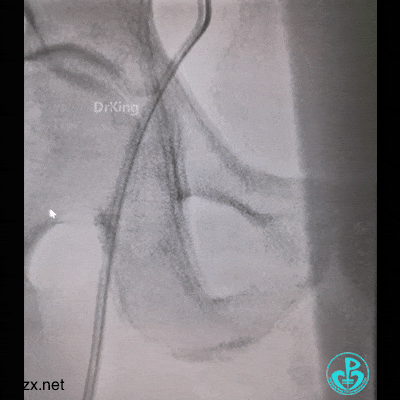

结果上面又出问题。

管子反折,J-W根本无法通过。

10分钟过去了,怎么办?

患者持续胸痛,先放这里,改入路开通心脏血管!